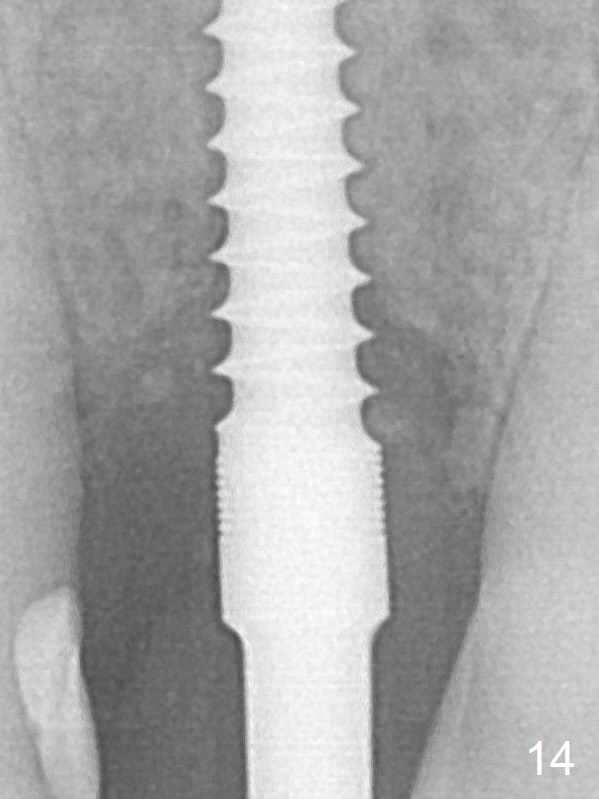

The peri-implant space (Fig.3) is filled with bone graft (Fig.4 *). The apical portion of the socket appears to have reduced 4 months postop (Fig.14). When the patient returns 1.5 years post cementation, there is increased bone density next to the coronal portion of the implant, equivalent to the bone graft (Fig.15 *). The crestal bone loss remains 2.5 years post cementation (Fig.17 *), although there is no sign of periimplantitis. Oral hygiene is poor.